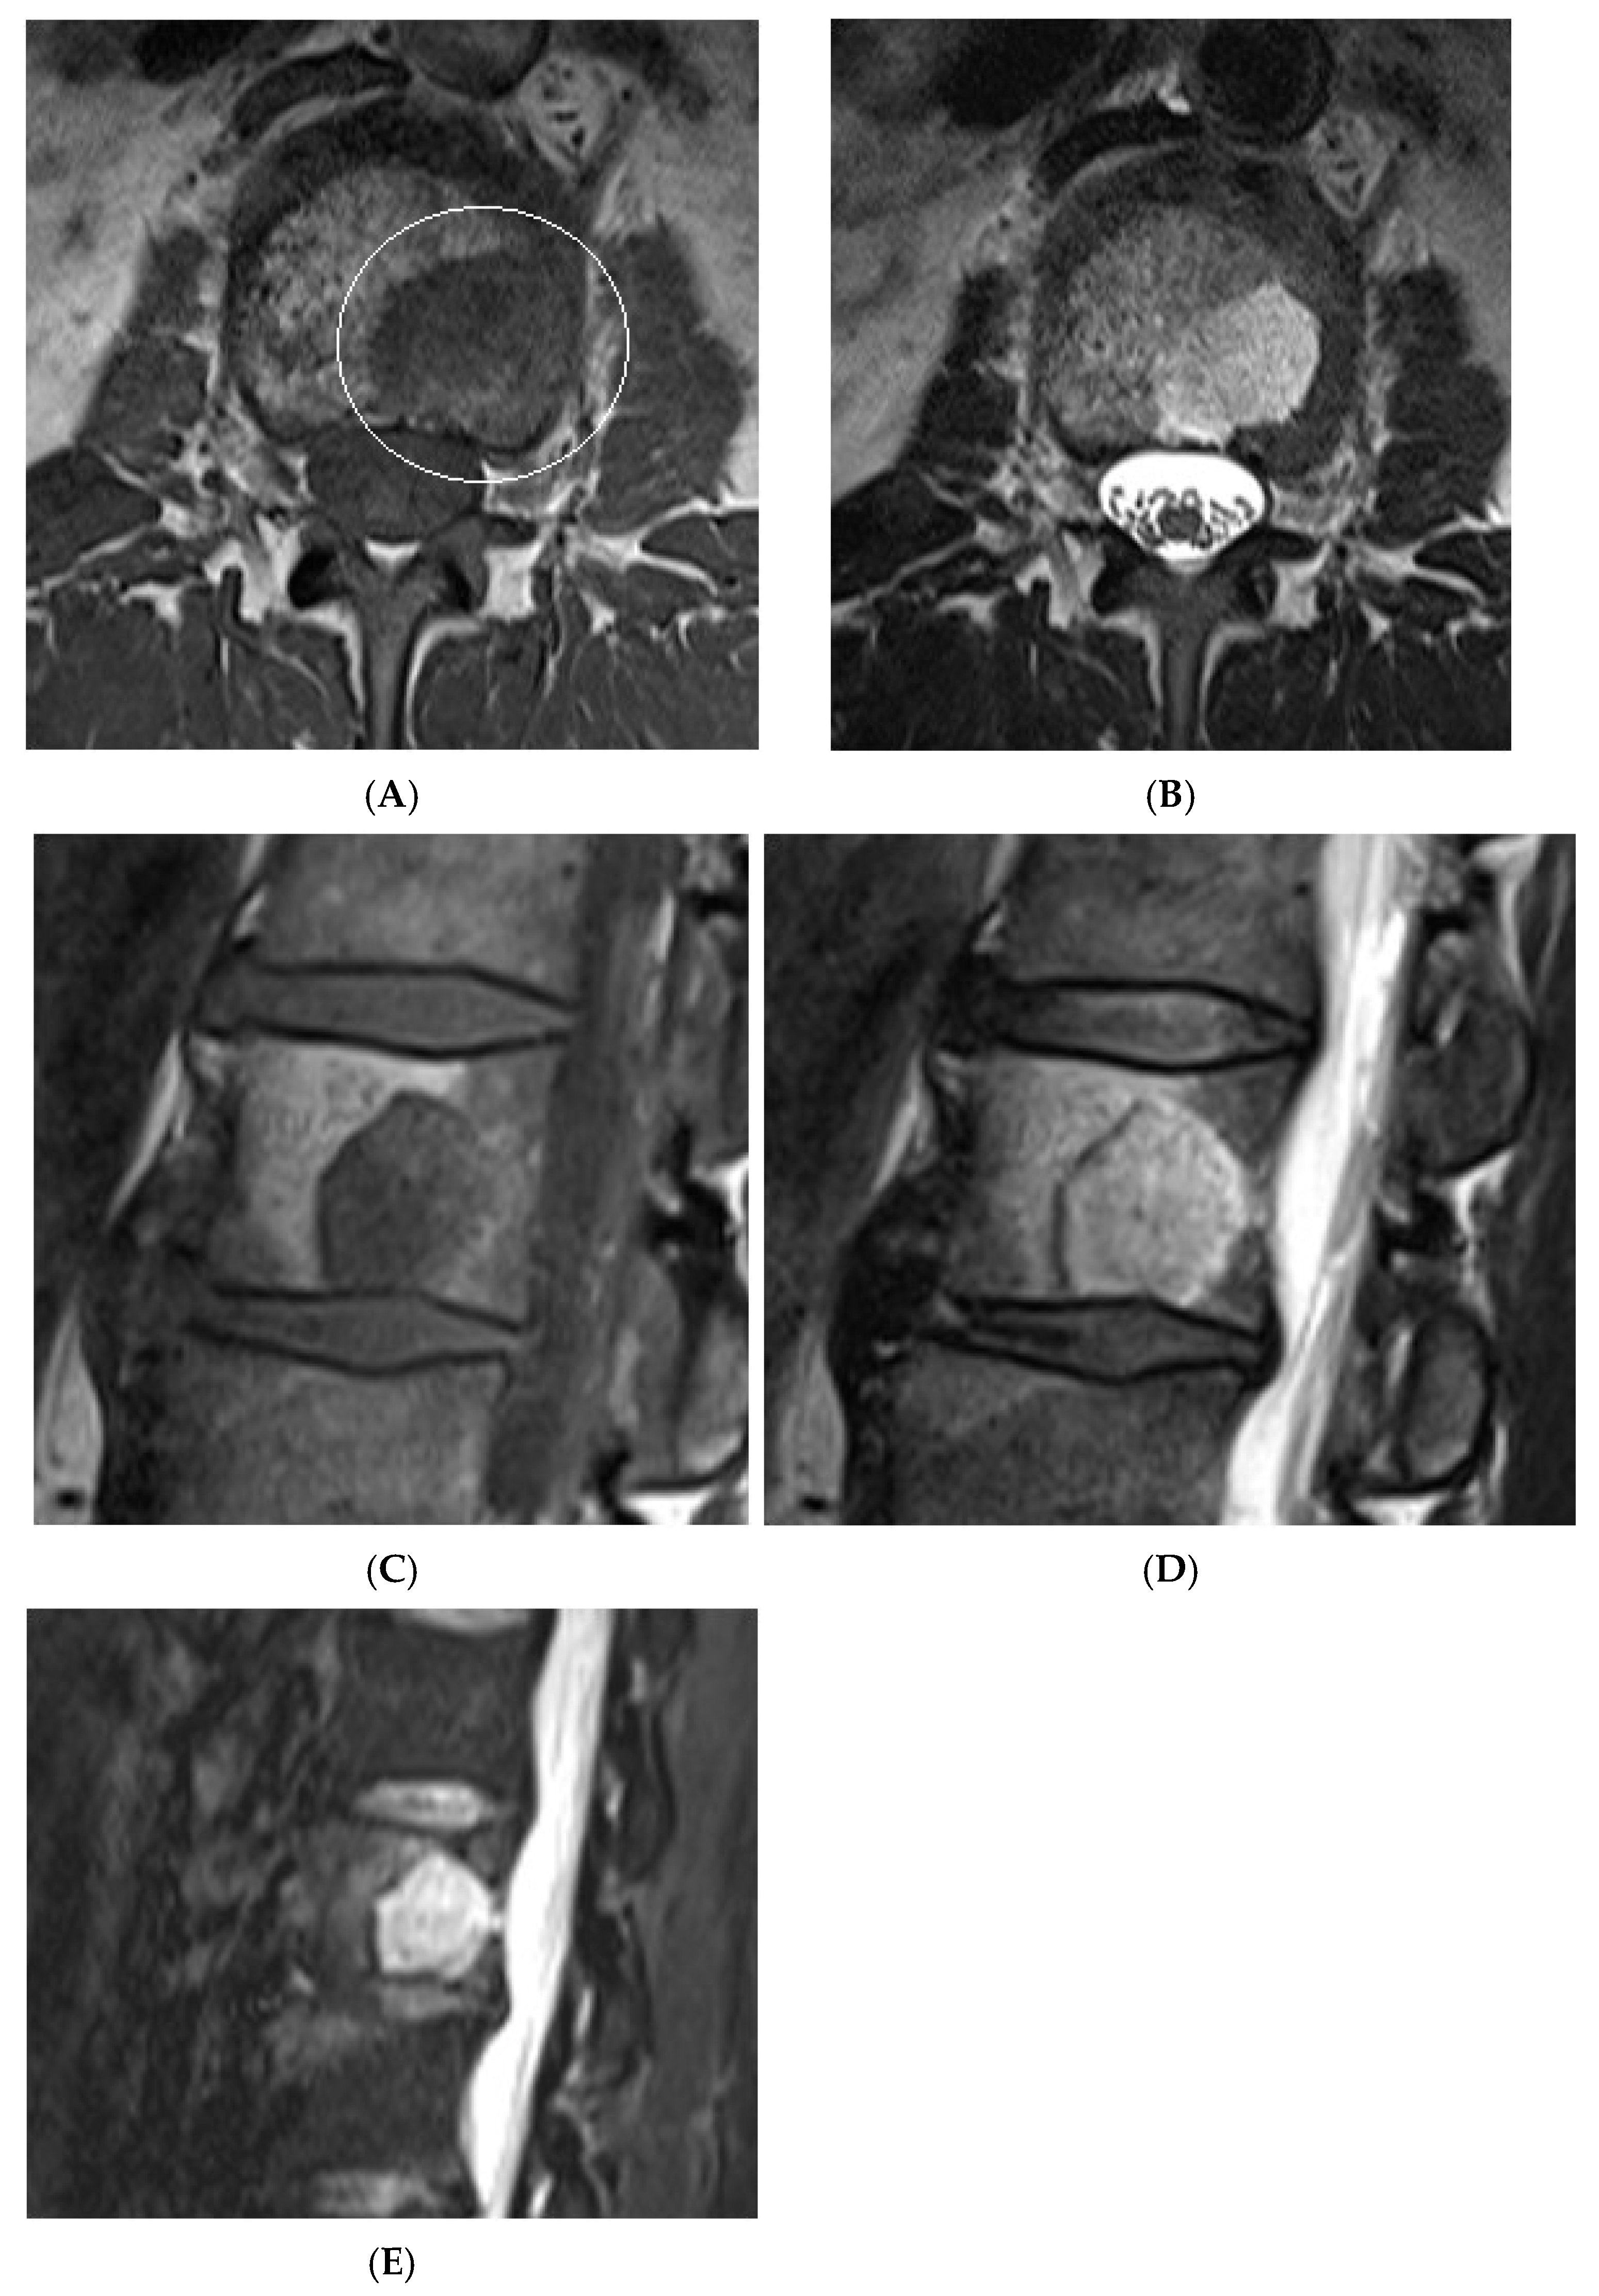

Collision Lesions: Typical and atypical haemangioma of vertebral body. (A) Axial T1W MRI demonstrating a classic haemangioma with a T1 hyperintense lesion occupying the vertebral body, with a smaller atypical T1 hypointense lesion (circled) adjacent, in keeping with an atypical haemangioma. (B) Axial T2W MRI with the same lesions—the atypical lesion to the left side of the patient (vertebral body) has a higher vascular component and therefore is more hyperintense than the adjacent and larger typical haemangioma. The larger lesion still remains hyperintense on T2, in keeping with predominant internal fat content. (C) Sagittal T1W spine MRI. (D) Sagittal T2W spine MRI. (E) Sagittal STIR spine MRI demonstrating fat suppression within the typical haemangioma with hyperintense signal within the atypical haemangioma as a collision lesion example.

Collision lesions of the spine are rare, with few documented cases involving the spinal cord. Notably, metastases from renal cell carcinoma to spinal hemangioblastomas in patients with Von Hippel–Lindau syndrome have been reported [21]. However, collision lesions specifically involving vertebral haemangiomas are exceedingly uncommon, with only a few cases of metastatic infiltration into haemangiomas described in the literature. These include metastases from renal cell carcinoma [22,23], colonic adenocarcinoma [24], and lymphoma [25], each leading to varying clinical manifestations, including spinal cord compression [25] (Figure 14, Figure 15 and Figure 16).